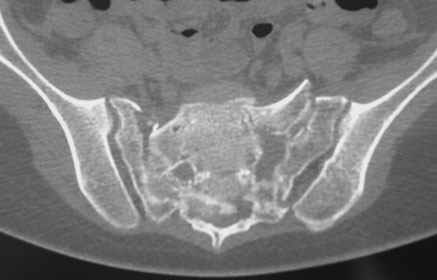

Травма 21.августа 2005г. На девочку в лесу упала береза. Доставлена в ближайшую ЦРБ. При поступлении установлен диагноз: Травматический шок 2-3 ст. Тупая травма живота. Забрюшинная гематома. Перелом костей таза с нарушением целостности тазового кольца. Перелом лонной и седалищной костей справа. Перелом поперечных отростков L3 - L5. Разрыв КПС справа. При поступлении выполнена диагностическая лапароскопия — выявлена обширная забрюшинная гематома. Было наложено скелетное вытяжение за бугристости обеих б/берцовых костей, больная уложена в гамак. Через неделю скелетное вытяжение демонтировано, гамак снят. Девочка уложена в положение «лягушки». Контрольные рентгенограммы через 4 недели после травмы. Заподозрен перелом дужки L5. Больная 26 сентября 2005 г. переведена в областную больницу в отделение детской ортопедии. При поступлении в локальном статусе: пальпация и перкуссия остистых и поперечных отростков L4-5 болезненная. Пальпация костей таза б/болезненная. С-м натяжения слабо положителен. Осевая нагрузка положительная. Движения в т/б суставах ограничены, болезненны. C-м прилипшей пятки отрицательный. C-м Ларрея и Варнейля отрицательный. Периферическая гемодинамика не нарушена.Неврологический статус: вторичная двусторонняя радикулопатия L5-S1. 29 сентября произведена компьютерная томография позвоночника и таза.

Судя по томограммам, радикулопатия может быть из-за компресии "конского хвоста" смещенным крестцовым позвонком, это хорошо видно на втором слева снимке. Если этот сегмент будет нестабилен и будет сохраняться неврологическая симптоматика, придется оперировать. Если неврологическая симптоматика уйдет и перелом стабилизируется, то можно обойтись без операции.